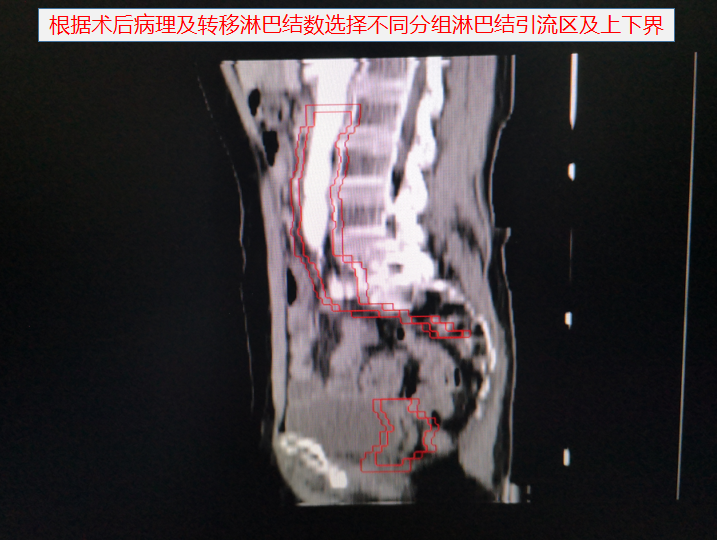

婦科腫瘤術後勾畫靶區示例: